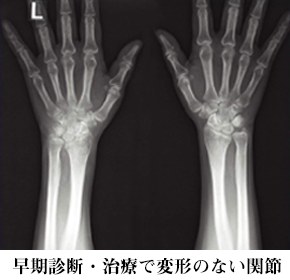

- ○最新のリウマチ検査・治療

- さて、そんな関節リウマチですが、ここ10年で診断と治療が目覚ましく進歩したのをご存知でしょうか?今まで難病のイメージの強かった関節リウマチですが、リウマチになっても仕事や家事をそのまま続けることが出来たり、お子さんを妊娠・出産されたり、元気に活躍されているリウマチの方が増えてきました。

リウマチの診断・治療が進歩させたのが、「関節エコー検査」と「生物学的製剤」になります。

しかしここ10年で「生物学的製剤」ができたことで、リウマチの痛みをとるだけでなく、関節で悪さしている免疫細胞を落ち着かせて骨の破壊や関節変形を起こさない治療ができるようになりました。生物学的製剤の中には、妊娠・授乳中も使用できる薬もあり、今まで妊娠中はステロイドホルモン剤が中心であった治療も大きく変わっています。